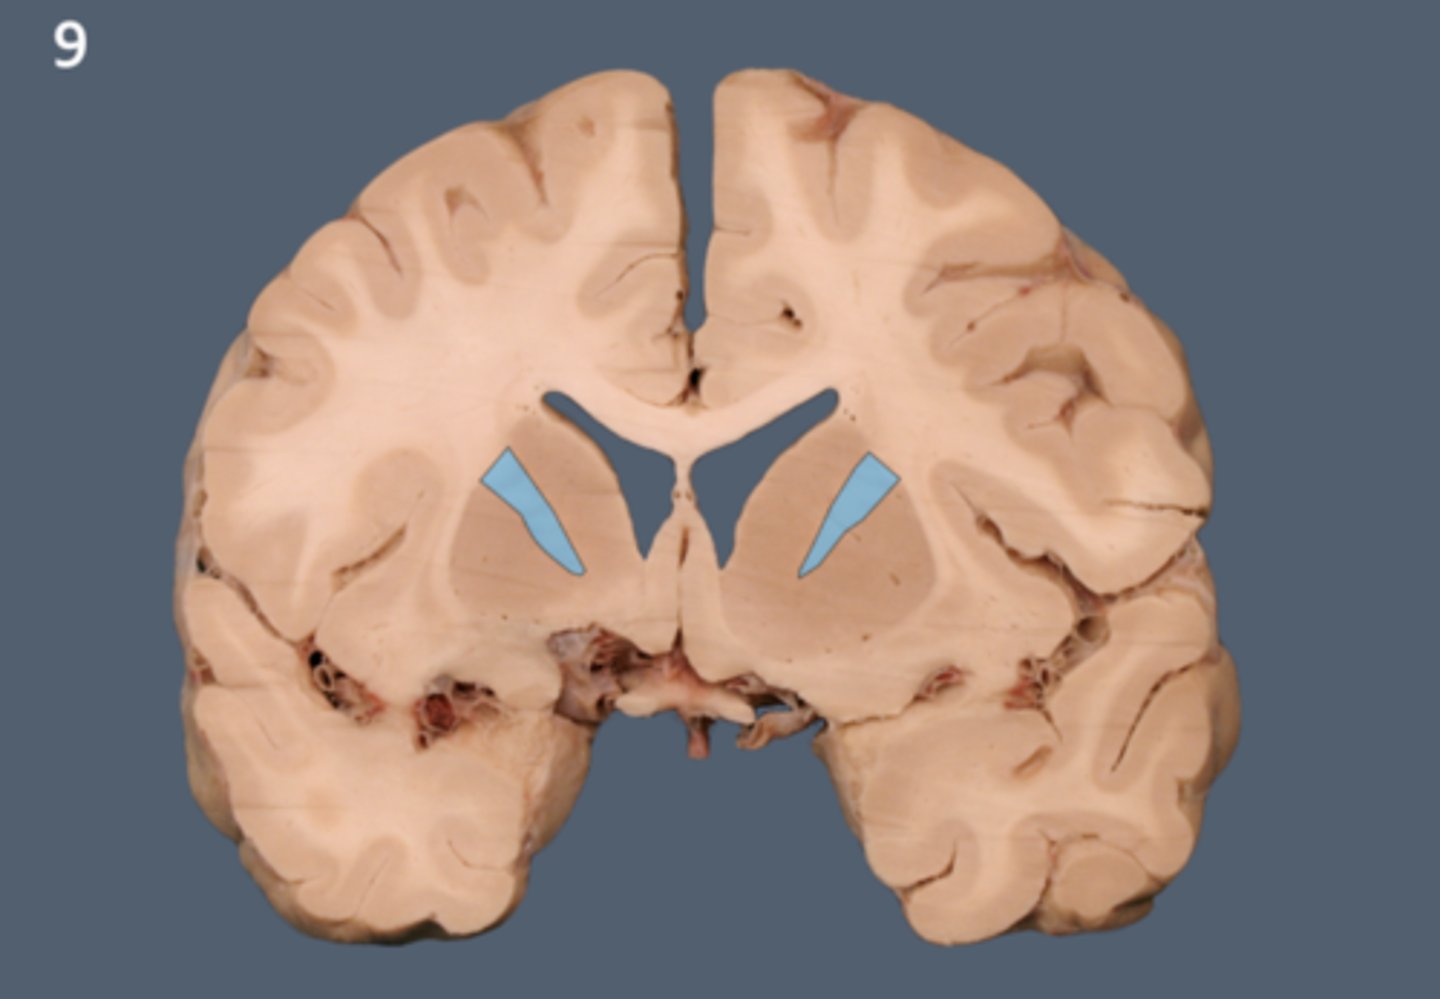

lateral ventricle

A complexly shaped lateral portion of the ventricular system within each hemisphere of the brain.

anterior horn of lateral ventricle

located in the frontal lobe and is the part of the lateral ventricle that lies in front of the interventricular foramen

body of lateral ventricles

located in the parietal lobe, situated between the anterior and posterior horns.

inferior horn of lateral ventricle

located in the temporal lobe of the brain. It is the largest of the three horns and extends from the atrium, curving anteriorly and inferiorly to go under the thalamus and into the temporal lobe

posterior horn of lateral ventricle

located in the occipital lobe of the brain, projecting backward. It is the most posterior part of the C-shaped lateral ventricle and lies deep within the occipital lobe.

interventricular foramen (of monro)

connects lateral ventricles to third ventricle

third ventricle

thin midline space that separates the left and right thalami.